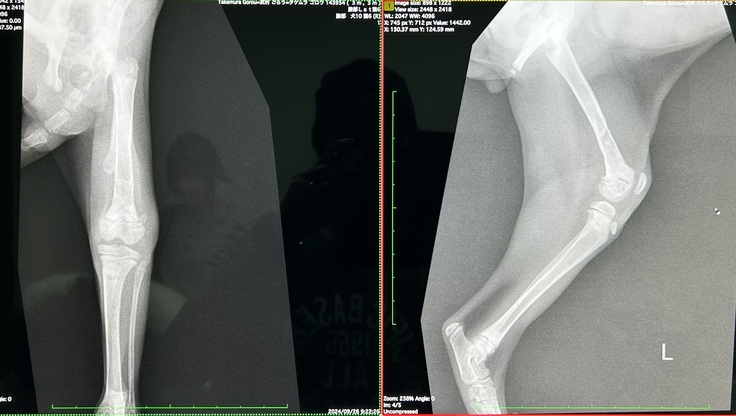

↓病院でのレントゲン写真

・太ももの裏側の状態は良くなってきました。

・ただ前側の筋肉が硬くなってきていたので、今度はそっちのマッサージを入念にとのことでした。

左脚の骨折部分は問題なく順調ですが、周りの筋肉の伸縮性が悪く、筋肉が固まってしまわないようにほぐすマッサージを継続中です。

左脚の機能は、座る時には外側に流れるように開き、歩く時はカクカクと力が逃げているような歩き方です。